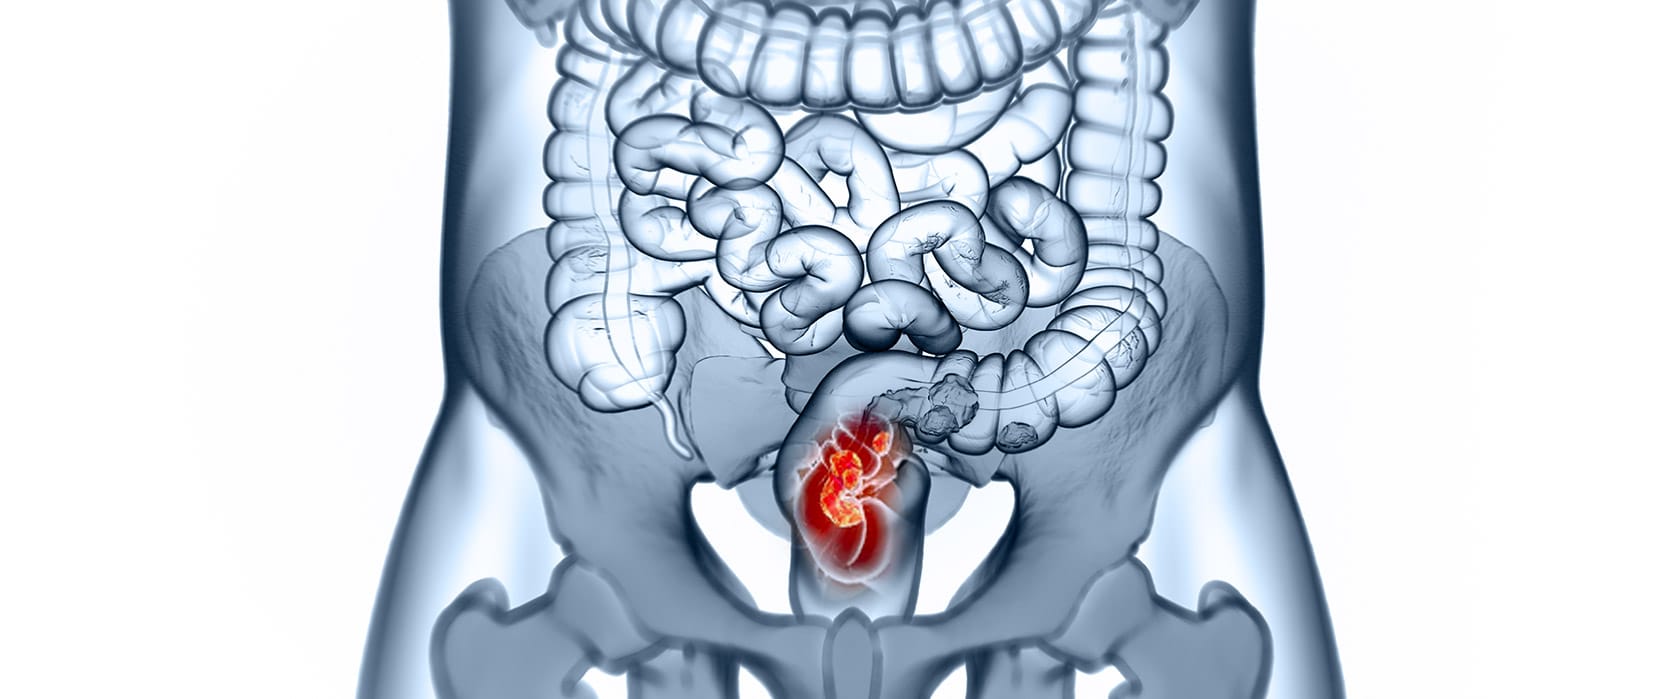

Рак прямой кишки — это злокачественное образование эпителиального происхождения, которое поражает нижний отдел толстого кишечника: в пределах 15 см от анального отверстия.

Заболевание занимает одно из лидирующих мест среди онкологических патологий желудочно-кишечного тракта. По данным Всемирной организации здравоохранения, эта патология занимает третье место по распространённости среди всех видов рака в мире, и ежегодно она диагностируется примерно у 1,9 млн человек. Рак прямой кишки — серьёзная медицинская проблема, которая требует своевременной диагностики и комплексного подхода в лечении. При этом значительная часть пациентов обращается к врачу уже на поздних стадиях болезни, когда терапия осложняется распространённостью опухолевого процесса.